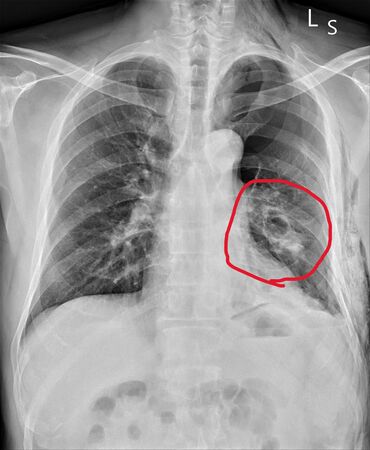

▲員榮醫療體系員榮醫院急診室翁聖富醫師解釋,張姓患者脾臟(圖中紅圈)破裂的情況。(圖/員榮醫院提供,下同)

接手處置個案的員榮醫院急診醫師翁聖富表示,張姓患者到急診時心跳110多下,正常的心跳是60到100下,心跳快其實是休克的早期表現,加上有氣胸左邊肚子也會痛,因此強烈懷疑會不會合併有內臟受損,內出血的可能,所以安排電腦斷層,結果發現患者除氣胸、肋骨四根骨折外,還合併有脾臟的破裂。

翁聖富指出,個案後續確認為脾臟三級破裂,合併腹腔積血,若未及時診斷與治療,恐因失血性休克而危及生命。由於情況危急,轉送醫學中心治療。而脾臟破裂要看受損的程度,如果相對輕微生命徵象也穩定的話,可以考慮用保守治療或者是用血管栓塞的方式,如果有休克症狀,生命徵象不穩定,就要考慮開刀把脾臟拿掉。